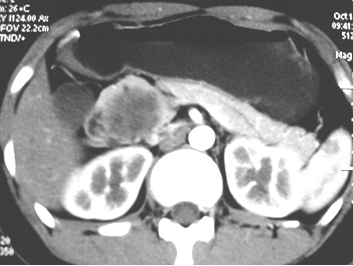

In combination with clinical findings, radiological features of SPT may help to make the correct diagnosis and differentiation from other pancreatic neoplasms. Abdominal ultrasound and CT scan usually demonstrate a huge, well-encapsulated mass with both solid and cystic components and displacement of nearby structures.15,17 Additionally, CT can play much more important role by providing further information about the size, location, the local invasion and vessel involvement of SPT, ultimately help to provide the final treatment strategy. In this study, on pre-contrasted CT, solid and cystic structures were demonstrated in 7 patients with SPT. After enhancement, solid and cystic structures were shown in 11 patients. Especially, the solid portions were moderately or obviously enhanced whereas the cystic parts remained unenhanced (Fig.1), which were consistent with those reported previously.9,11,18 It was mentioned accompanying CBD dilation and intra tumor calcification were infrequent findings in SPT patients.9,11,15,19 In our study, only one SPT patient with a tumor located in the pancreatic head presented with dilation of CBD. Of note, internal or capsular calcification was shown in 5 patients (Fig.2), suggesting the role of calcification on the development of SPT might need to be further investigated. Considering the superiority of MRI in terms of correlation between radiological and clinicopathological findings in SPT, MRI was strongly proposed for the diagnosis of SPT.6,10,18 Consistently, in our study, the diagnosis of SPT suggested by MRI was ultimately confirmed pathologically.

Fig 1

The CT scan demonstrated the solid portion of SPT was moderately or obviously enhanced whereas the cystic part remained unenhanced